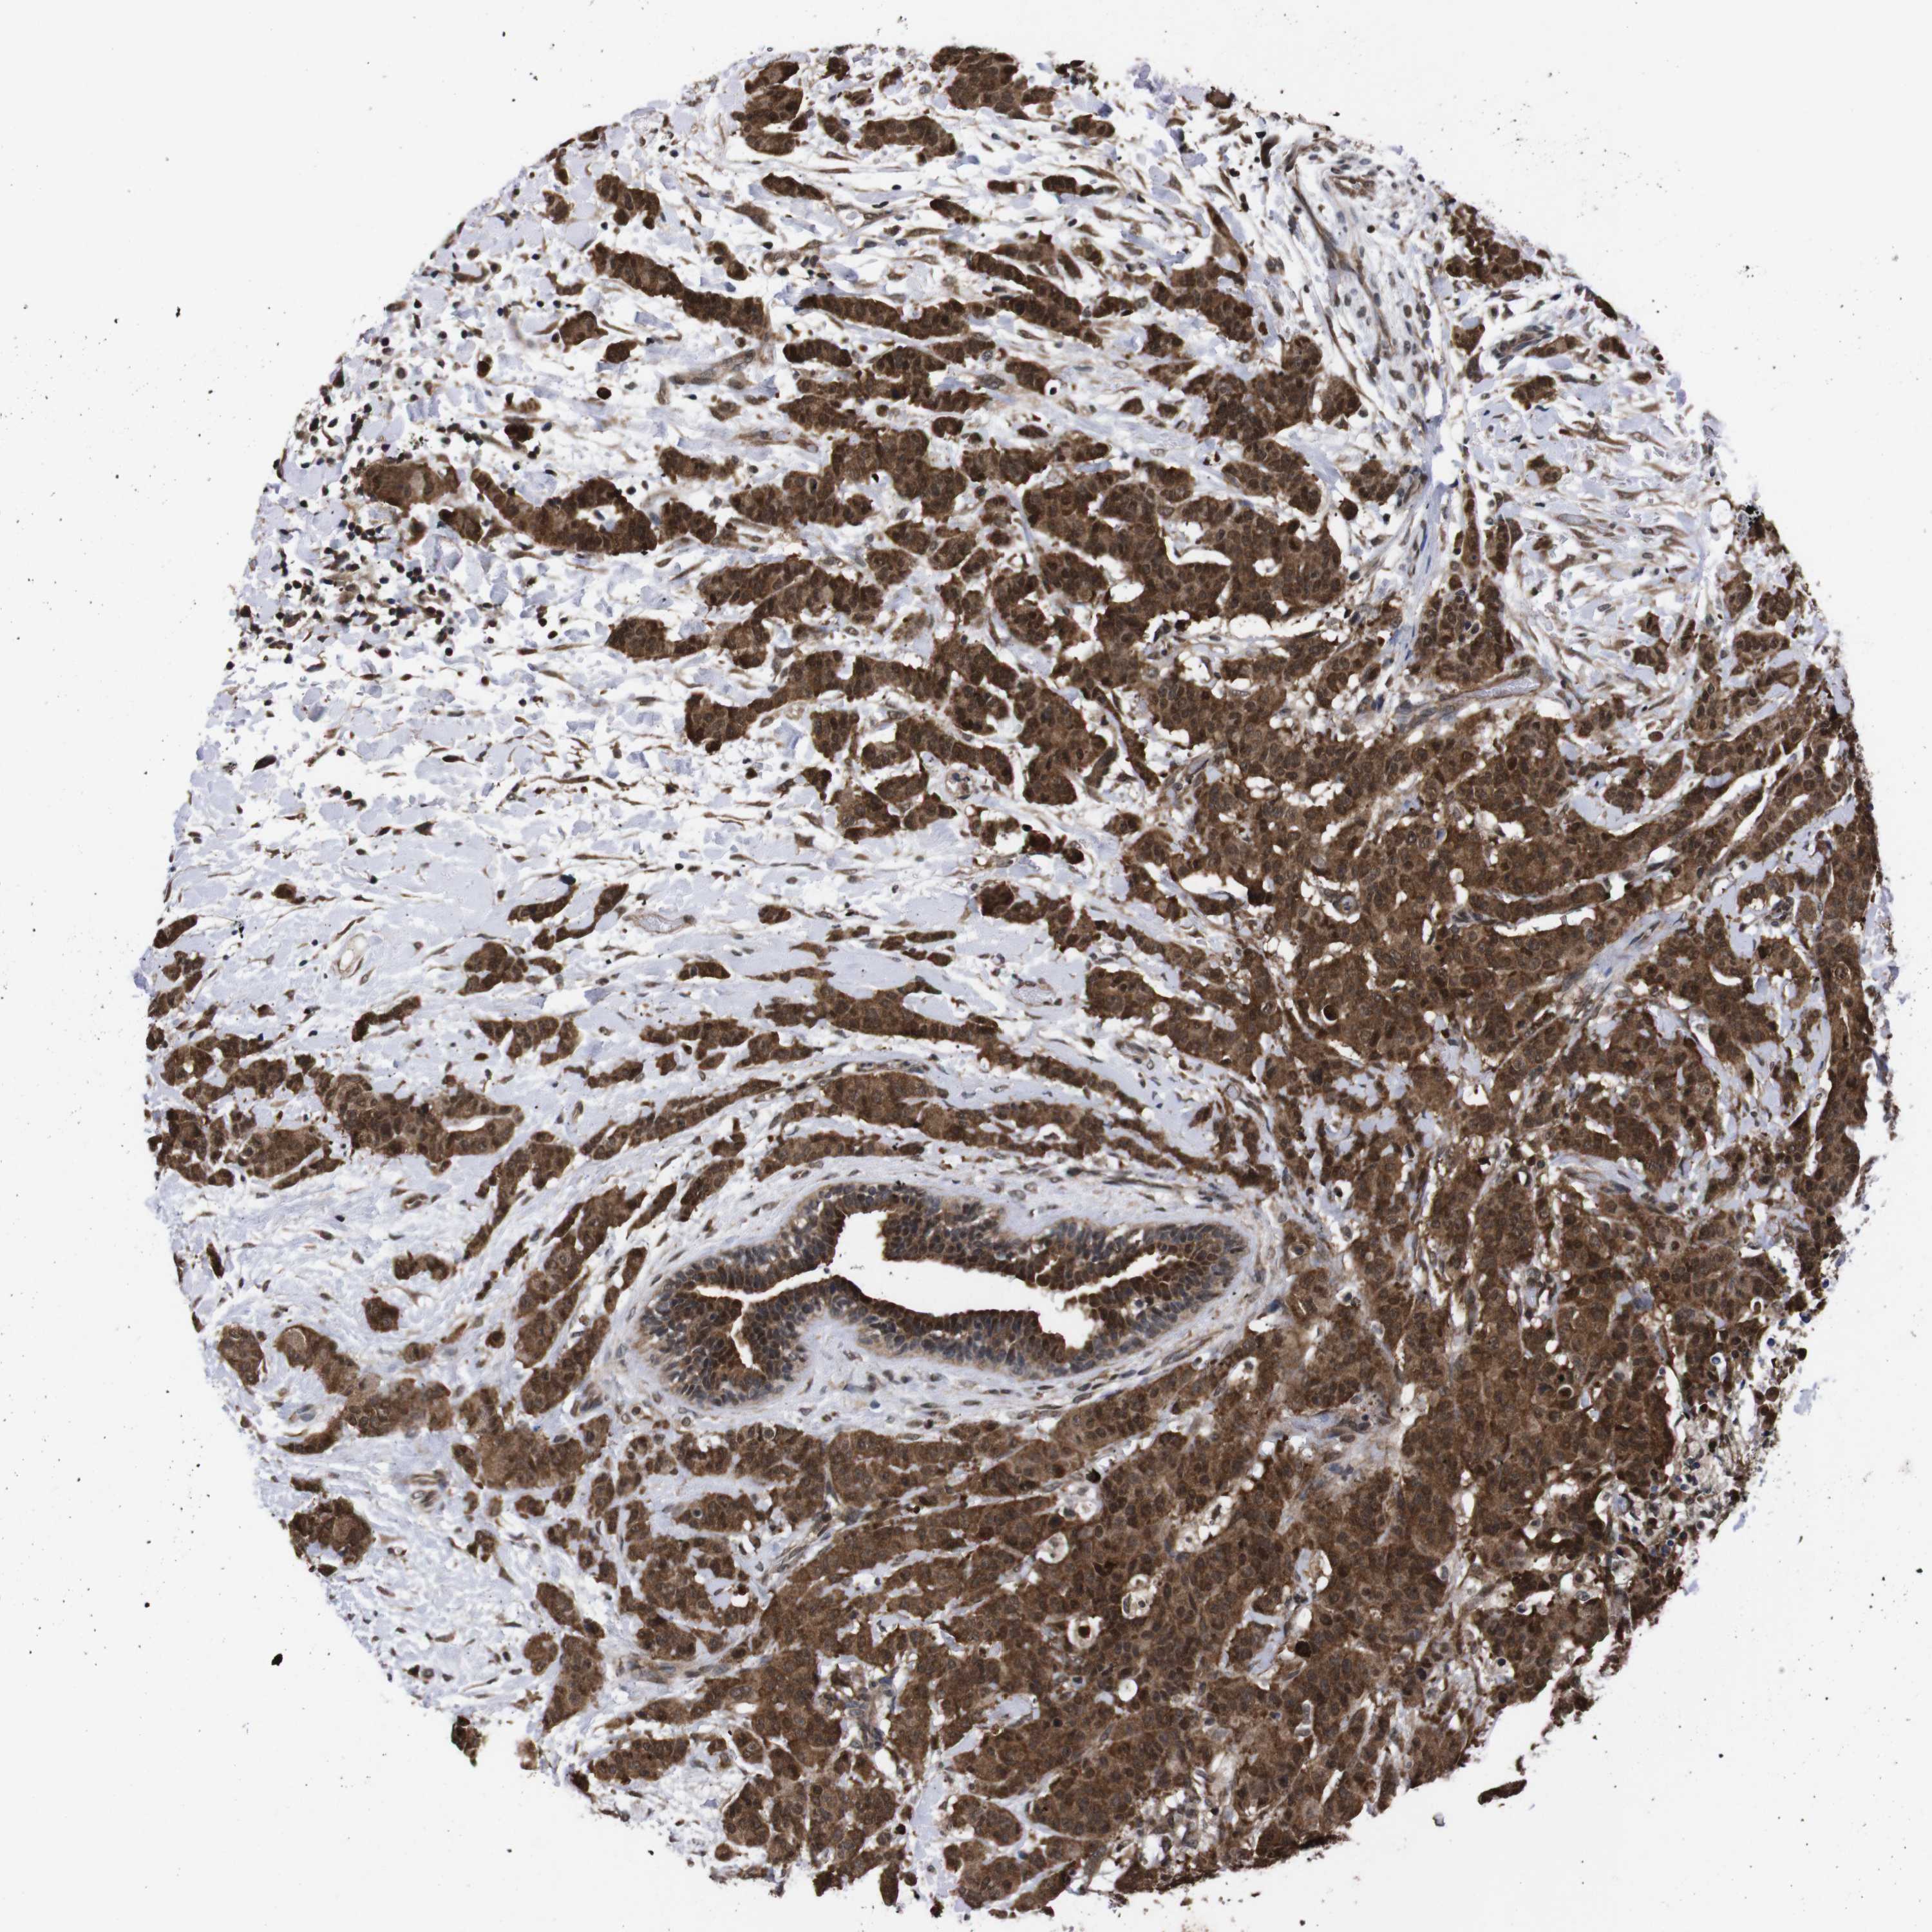

BRCA TCGA BRCA VALIDATION PROTEIN EXPRESSION